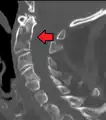

Fracture of dens

Fractures of the dens, not to be confused with Hangman's fractures, are classified into three categories according to the Anderson Alonso system:

• Type I fracture - Extends through the tip of the dens. This type is usually stable.

• Type II fracture - Extends through the base of the dens. It is the most commonly encountered fracture for this region of the axis. This type is unstable and has a high rate of non-union.

• Type III fracture - Extends through the vertebral body of the axis. This type can be stable or unstable and may require surgery.